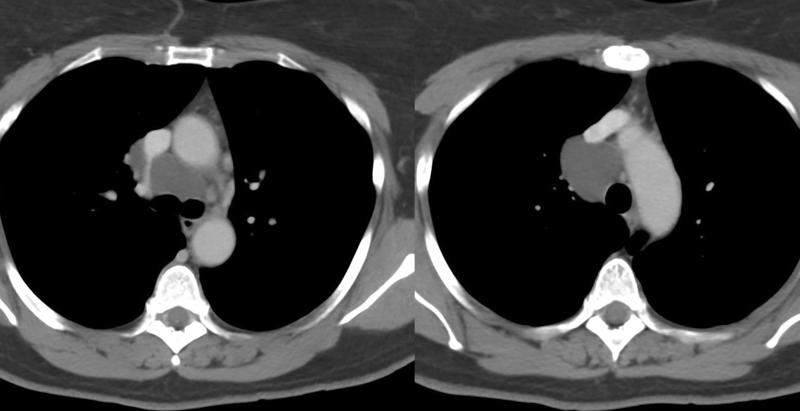

Bronchogenic cyst CT